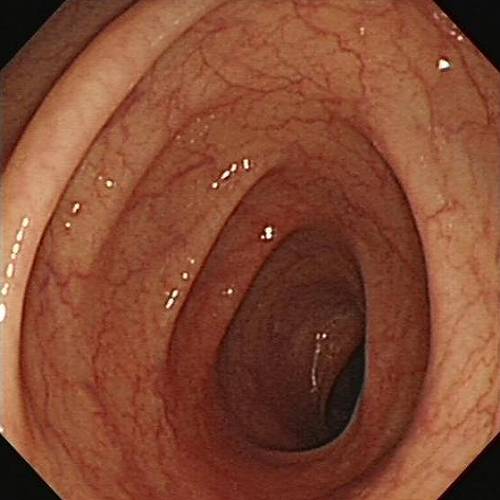

▲ 正常人的结肠VS 黑变病结肠

医生给小蔡做了肠镜,没想到,肠壁上到处都是星星点点的黑斑,就是肠粘膜反复受损所致。而更不幸的是,医生发现了其中一块黑斑竟已癌变。